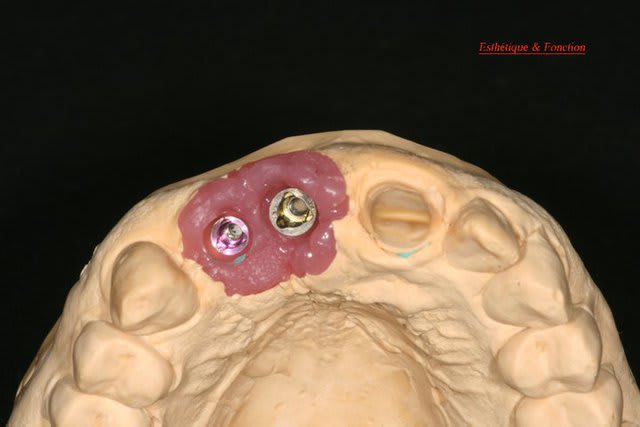

Bon ben j'ai implanté avant d'avoir refait la 21. Du coup j'ai mésialé la pose de 11 pour compenser la distalisation de 21.

Au final je n'ai pas fait de greffe osseuse... et j'ai réalisé une technique de rouleau sur 11-12 mais je reste un peu court à mon goût.

J'ai mis en place des transitoires sur 11-12-21 pour temporiser 3 mois pour voir la maturation des tissus mous.

Je réaliserai dans un second temps des piliers procera.

Je mets quelques photos de la patiente au cab et du prothèsiste d'Epinal.

La vraie difficulté a été de retrouver le milieu incisif pour déterminer la position des implants.

Les provisoires sont solidaires ? ( bravo pour le parallélisme)